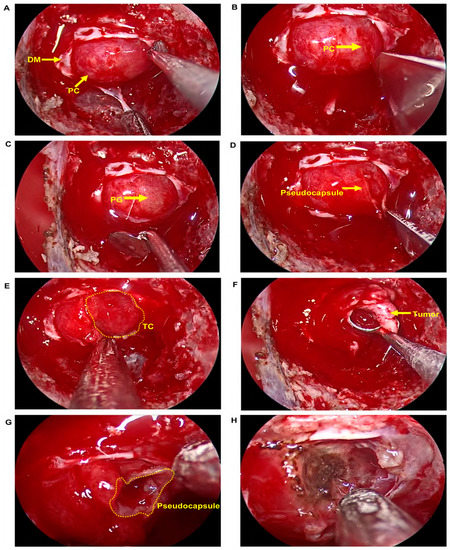

- Nagata, Y.; Takeuchi, K.; Yamamoto, T.; Ishikawa, T.; Kawabata, T.; Shimoyama, Y.; Inoshita, N.; Wakabayashi, T. Peel-off resection of the pituitary gland for functional pituitary adenomas: Pathological significance and impact on pituitary function. Pituitary 2019, 22, 507–513. [Google Scholar] [CrossRef] [PubMed]

- Zhou, Y.; Wei, J.; Feng, F.; Wang, J.; Jia, P.; Yang, S.; Gao, D. Pseudocapsule-Based Resection for Pituitary Adenomas via the Endoscopic Endonasal Approach. Front. Oncol. 2022, 11, 812468. [Google Scholar] [CrossRef] [PubMed]

- Wang, X.B.; Han, T.Y.; Ma, J.G.; He, C.; Xue, L.; Zhang, X.; Wu, Z.B. Pseudocapsule and pseudocapsule-based extracapsular resection in pituitary neuroendocrine tumors. Front. Endocrinol. 2022, 13, 1056327. [Google Scholar] [CrossRef] [PubMed]

- Oldfield, E.H.; Vortmeyer, A.O. Development of a histological pseudocapsule and its use as a surgical capsule in the excision of pituitary tumors. J. Neurosurg. 2006, 104, 7–19. [Google Scholar] [CrossRef]

- Qu, X.; Xu, G.; Qu, Y.; Song, T. The pseudocapsule surrounding a pituitary adenoma and its clinical significance. J. Neuro-Oncol. 2011, 101, 171–178. [Google Scholar] [CrossRef]

- Monteith, S.J.; Starke, R.M.; Jane, J.A., Jr.; Oldfield, E.H. Use of the histological pseudocapsule in surgery for Cushing disease: Rapid postoperative cortisol decline predicting complete tumor resection. J. Neurosurg. 2012, 116, 721–727. [Google Scholar] [CrossRef] [PubMed]